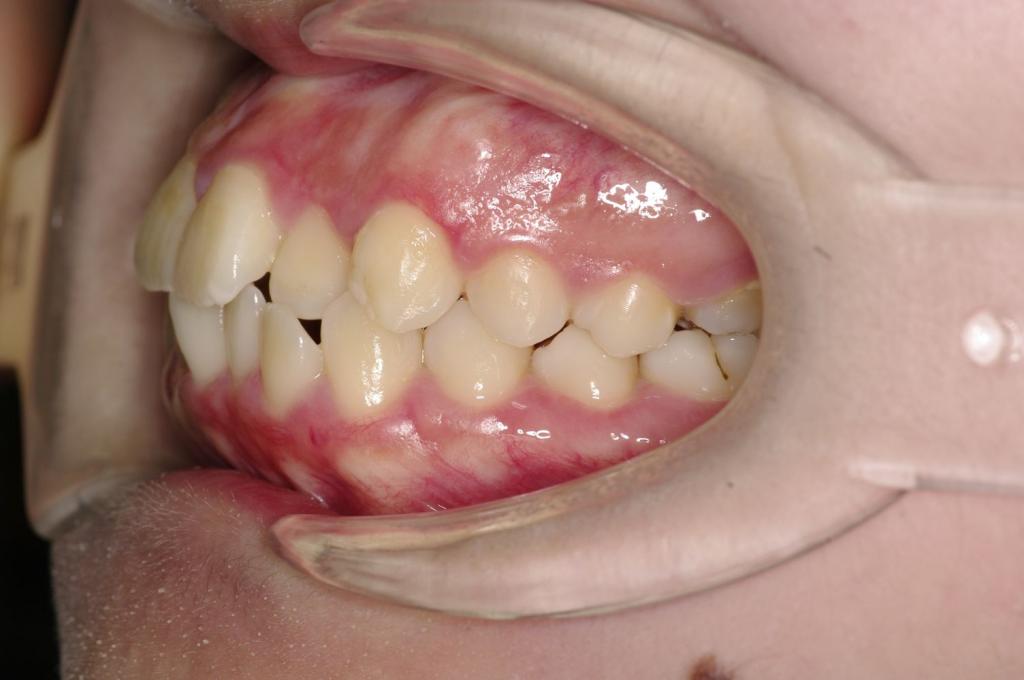

前歯、出っ歯・開咬の矯正治療

(治療期間、治療前後写真、治療方法、費用)WORKS